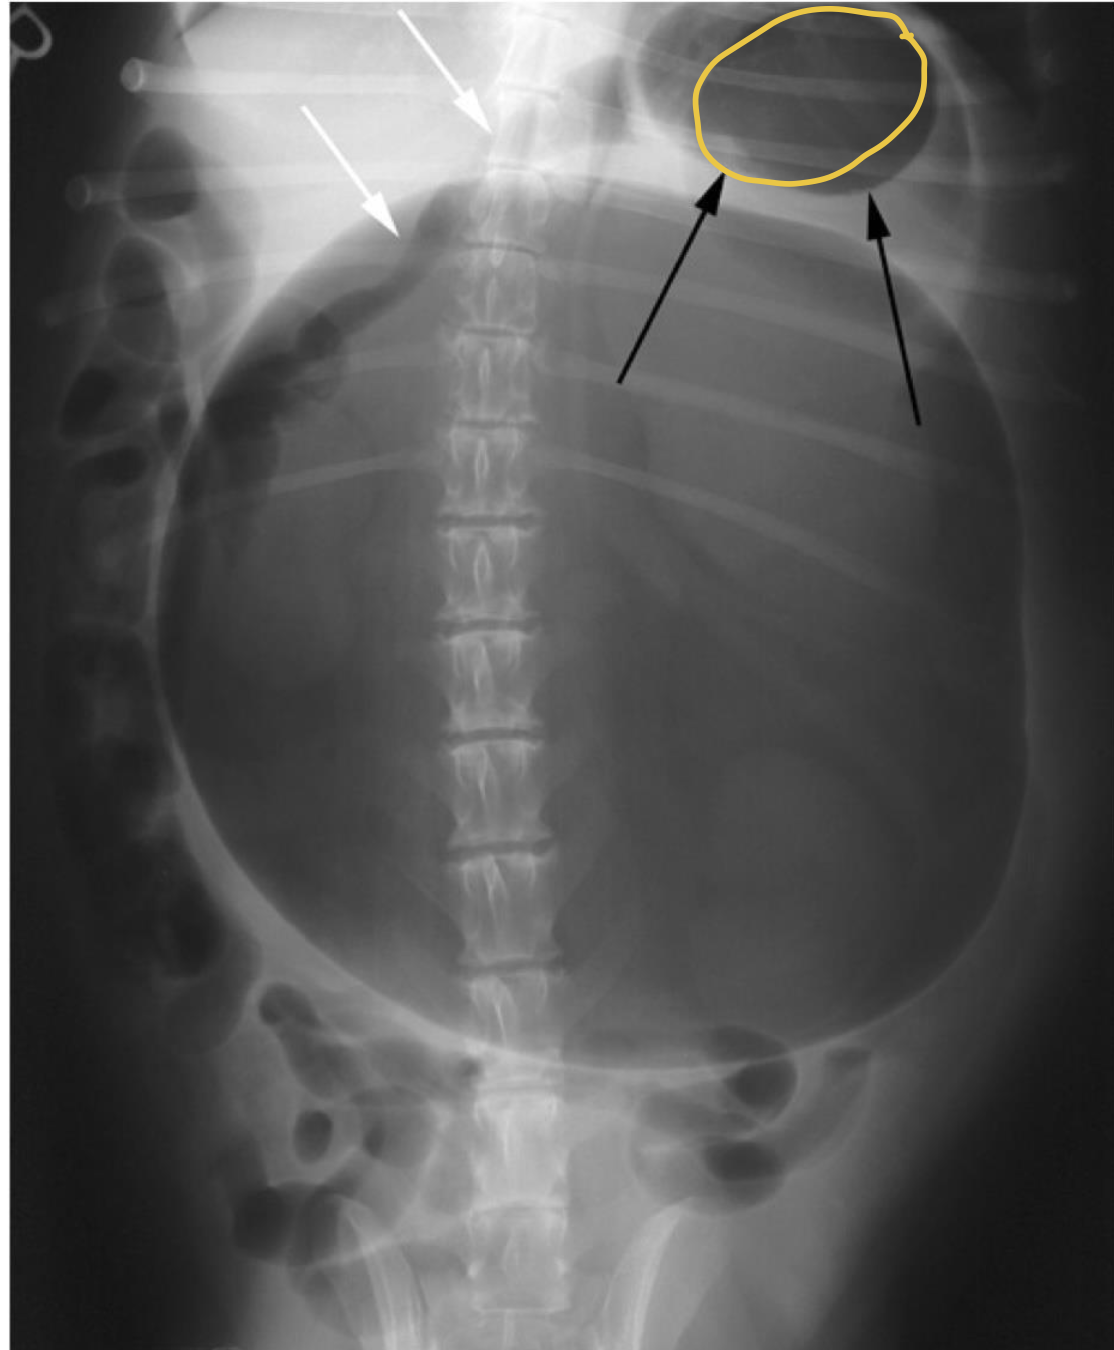

what does the radiograph show?

gastric volvulus displacing pylorus to dorsal left

displacement of pylorus from gastric voluvulus